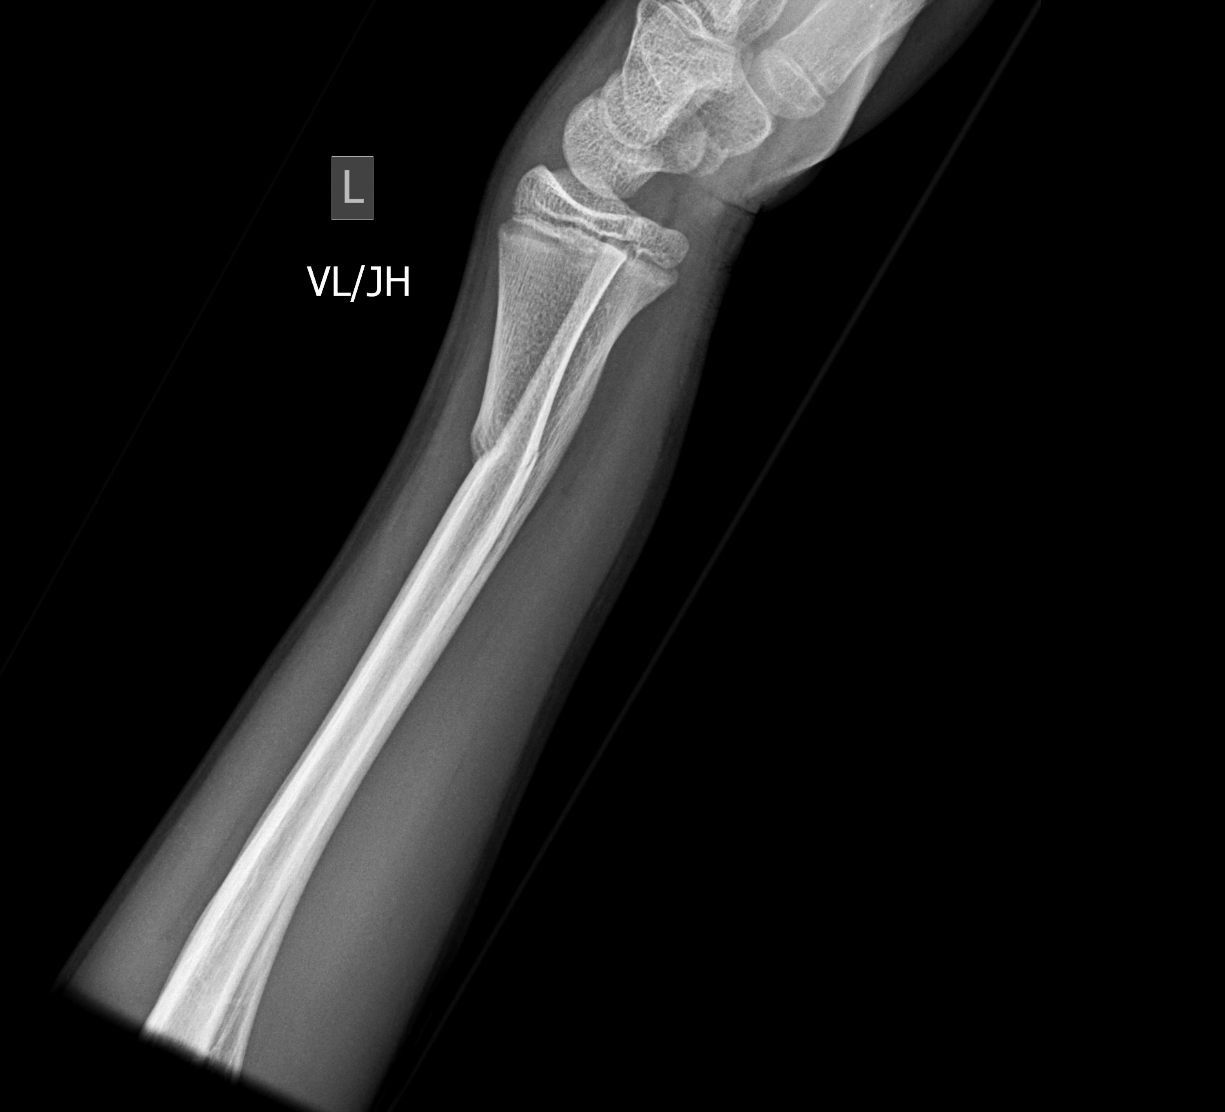

Findings

Bone

Growth plates, ossification centers, apophyses

Joints and alignment